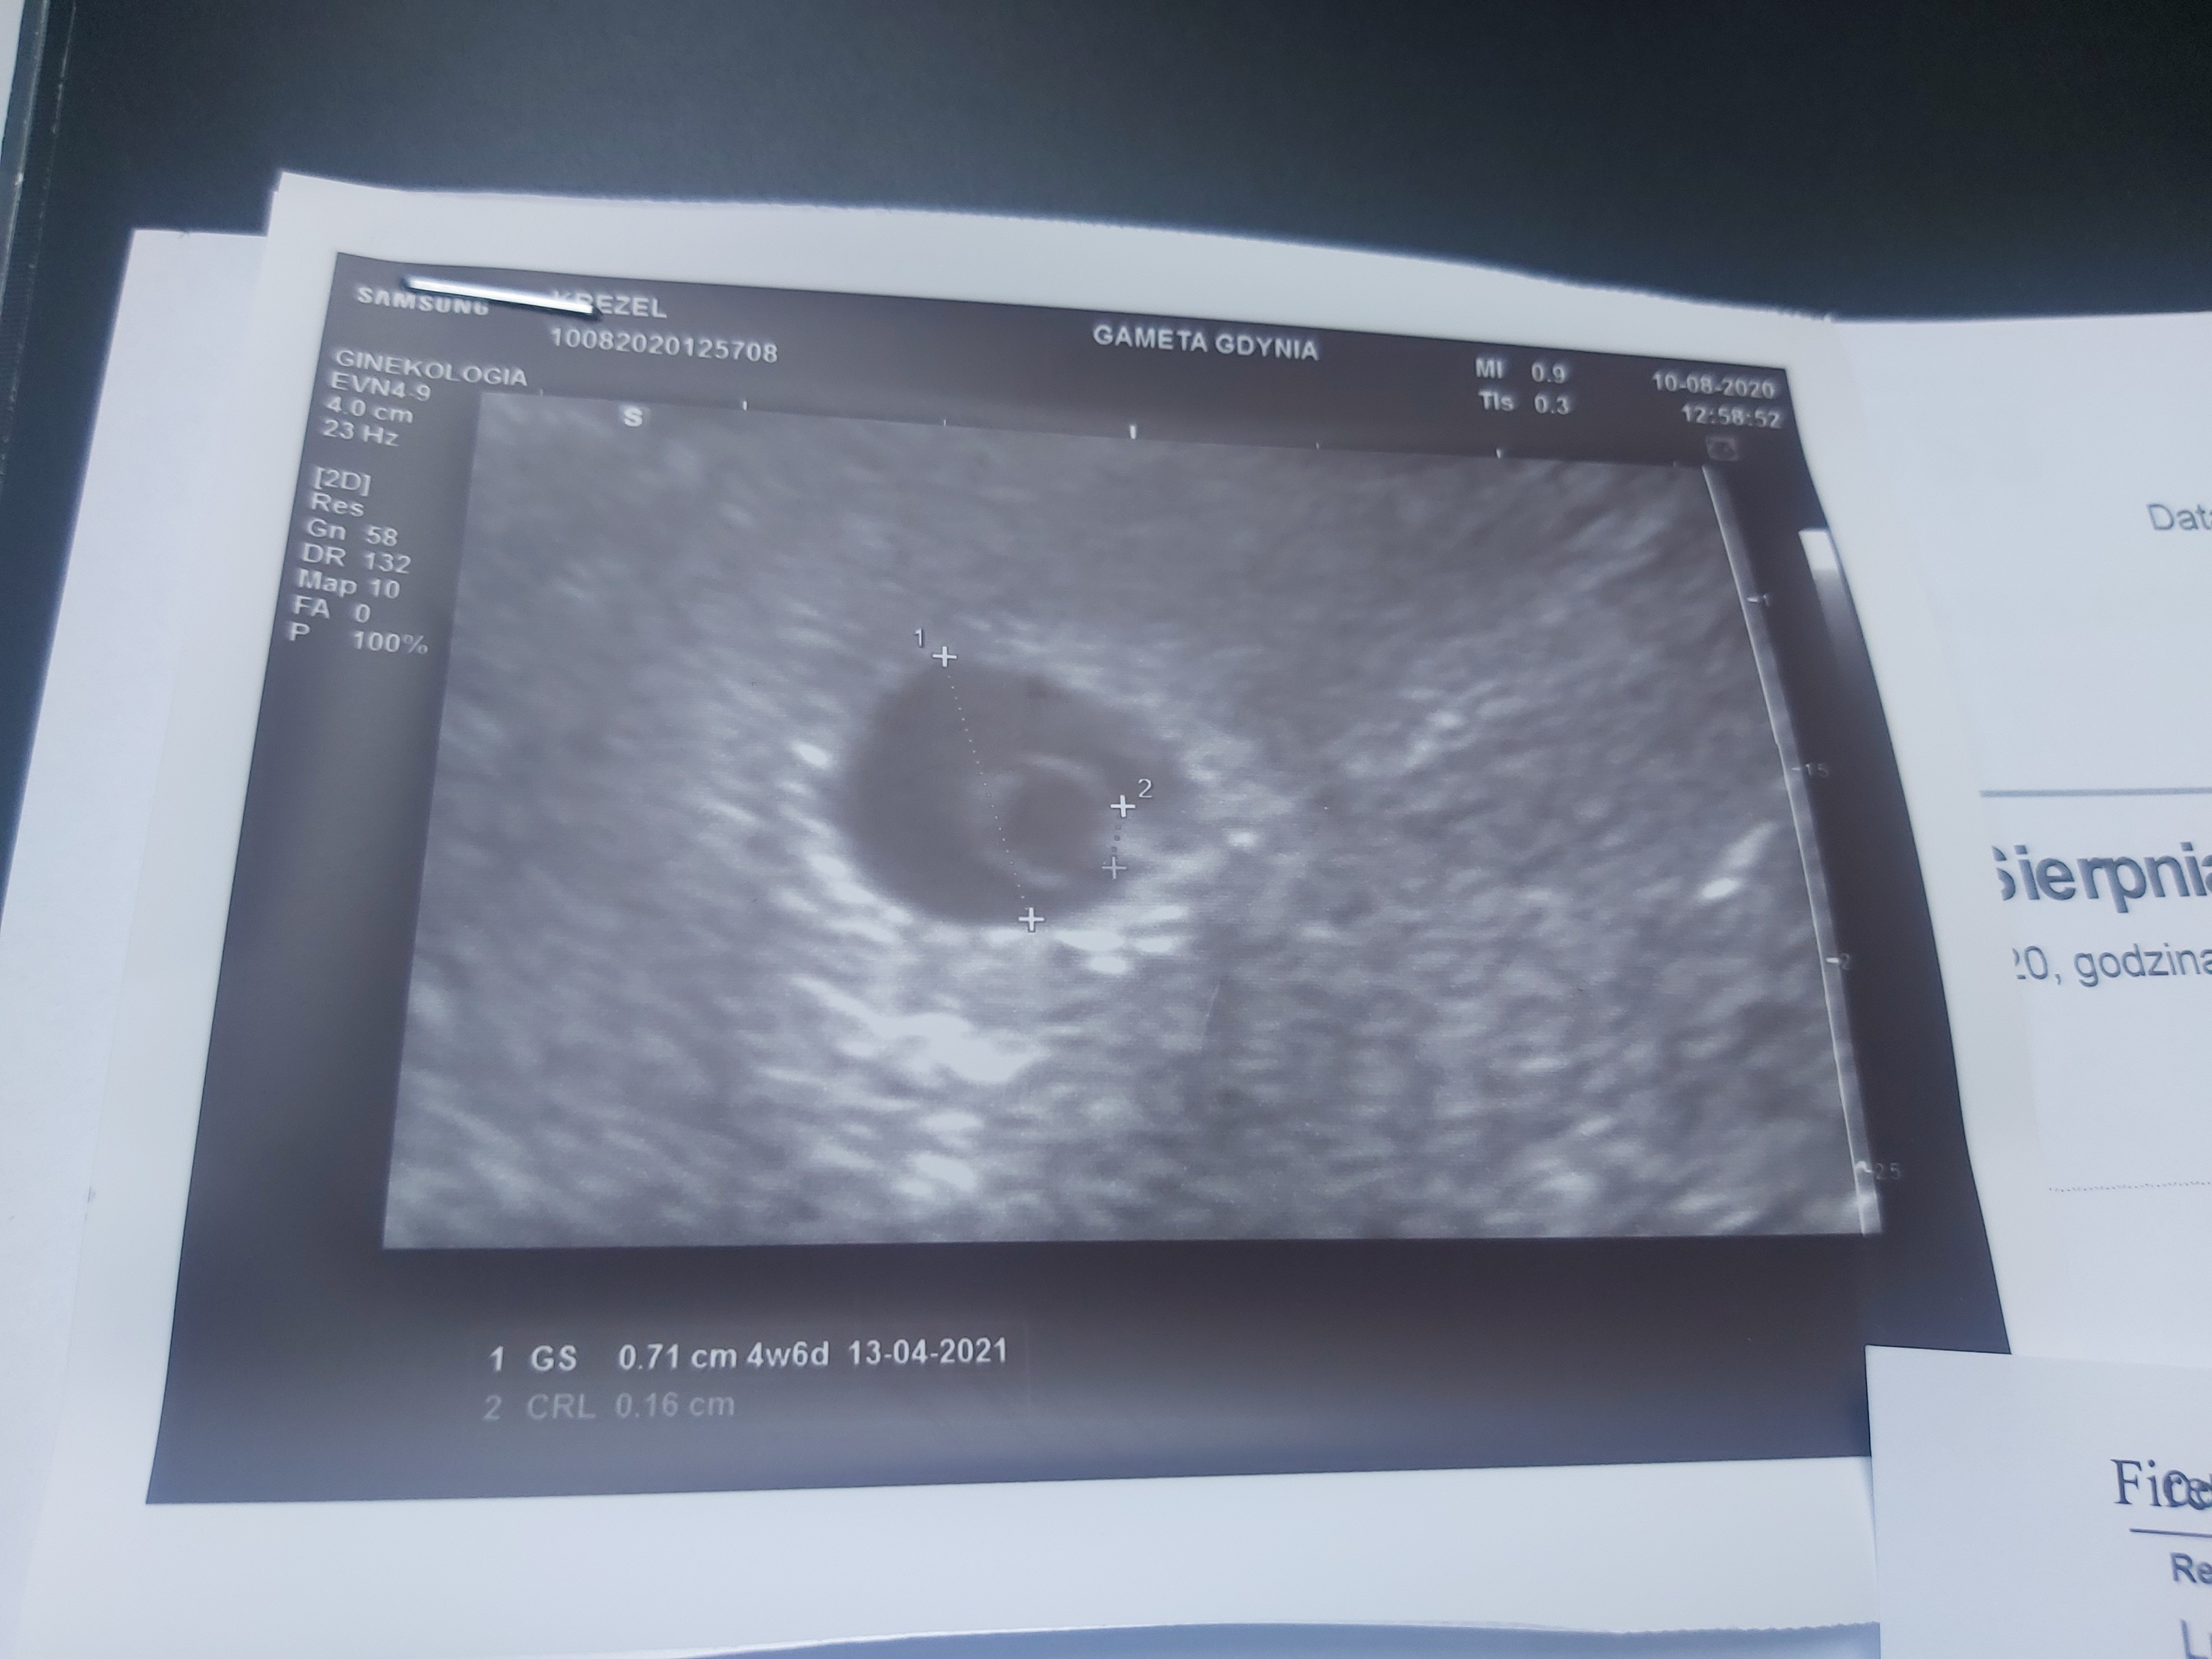

Ja już po wizycie. Pęcherzyk ciazowy jest. Lekko wyczuwane tętno. Uczucie niesamowitewracamy za tydzień we wtorek na wizyte serduszkowa